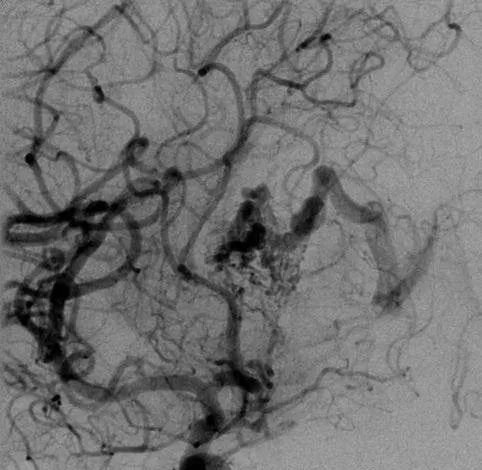

该AVM由ACA/PcaA分支、ACoA穿支和mPChA供血[右侧ICA造影

▼侧位s,前斜位